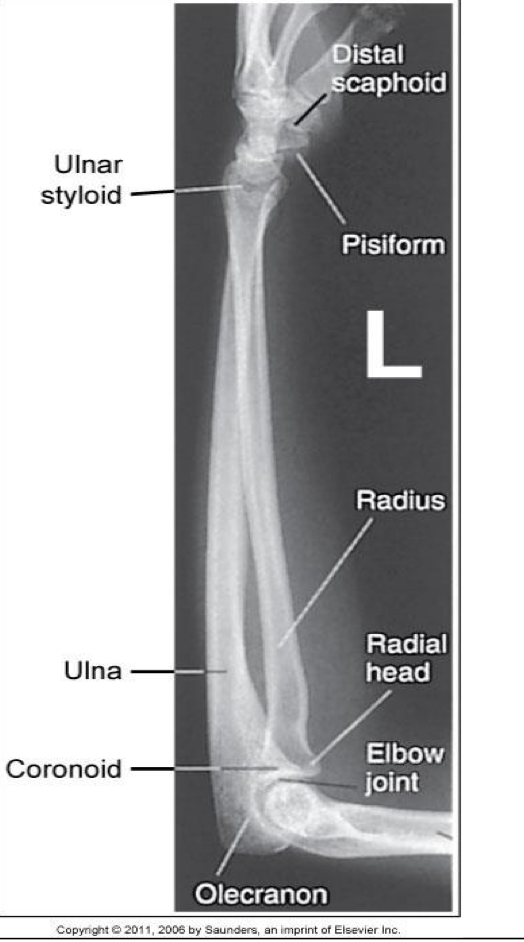

Lateral Forearm -Lateromedial Projection

Patient Position

Similar to wrist

Patient sitting at side or end of table

Humerus abducted, elbow flexed 90 o

Entire upper limb at same height

Part Position

Wrist is placed in a lateral

Thumb side up (lateromedial)projection

CR

To midforearm

Collimation

o Same as for AP projection

Evaluation Criteria for lateral forearm

• Carpals and distal humerus included

• Elbow flexed 90°

• Head of ulna superimposed over radius

• Radial head superimposed by coronoid

• Radial tuberosity is superimposed over medial radial shaft

• Humeral epicondyles are superimposed